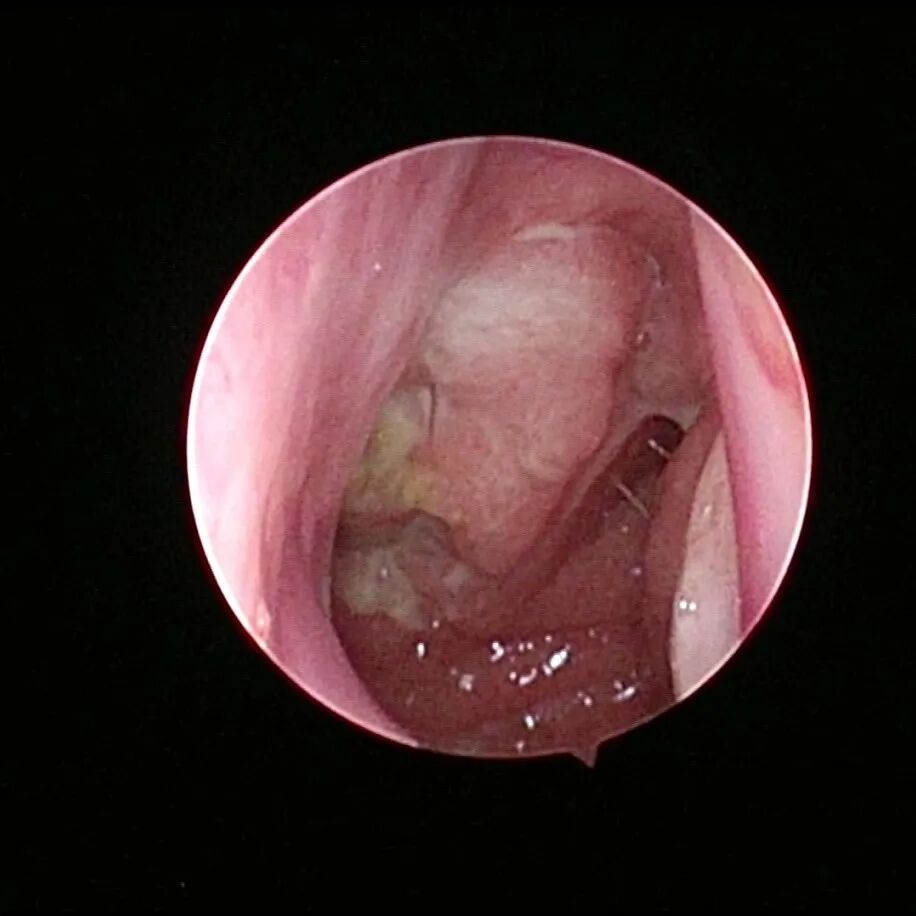

成人腺样体残体

2